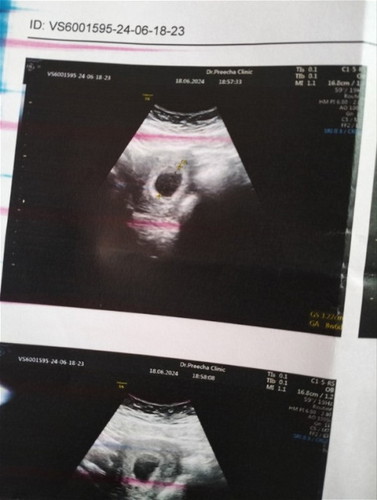

แม่ๆเจอน้องช้าสุดกี่วีคค่ะ หมอนัดอีก2สัปดาห์ ถ้ายังไม่เจอน้อง มีโอกาสท้องลมค่ะ ในรูป 8วีค6วันค่ะ

รู้อีกที9วีคค่ะ เห็นตัวน้องค่ะ🩷